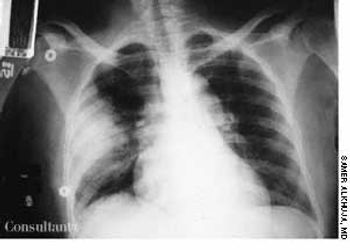

A 35-year-old man, a smoker, had right pleuritic pain, productive cough, and fever for 3 days. His pulse rate was 107 beats per minute; respiratory rate, 14 breaths per minute; blood pressure, 136/80 mm Hg; and temperature, 37.7°C (99.9°F). There were signs of right upper lobe consolidation. Laboratory studies showed hyponatremia. Chest films showed a homogeneous density in the right upper lobe.